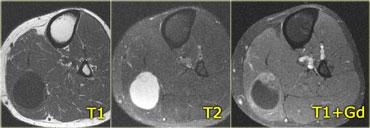

Hình bên trái là một bệnh nhân khác với viêm cơ nốt khu trú, trông giống như bất kỳ khối nào khác trên chuỗi xung T1W, T2W và sau tiêm thuốc tương phản từ.

Với tiền sử u lympho, có thể gợi ý viêm cơ nốt khu trú, nhưng không có gì mang tính quyết định từ các hình ảnh này.

Chuỗi xung T1W có ức chế mỡ sau tiêm thuốc tương phản từ – Các ổ tụ dịch bên trong cơ ngấm thuốc ở bệnh nhân viêm mủ cơ